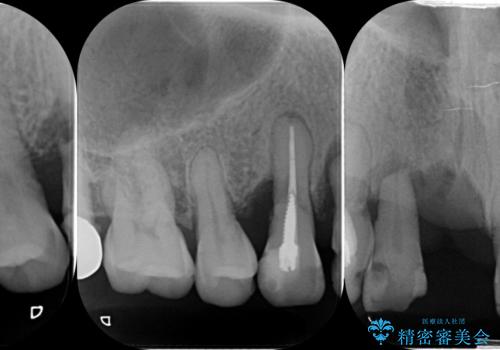

咬合性外傷による歯槽骨吸収 ブリッジ補綴

- 歯が揺れしっかりとものが噛めないことの改善を求めて来院されました。

保存の難しい歯の抜歯、保存できる歯の歯周病治療、欠損部位の歯槽堤形態回復を含めブリッジによる安定した咬合機能回復を計画します。